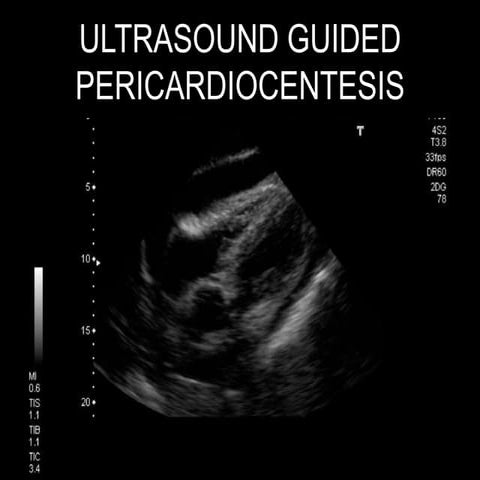

Ultrasound Guided Pericardiocentesis